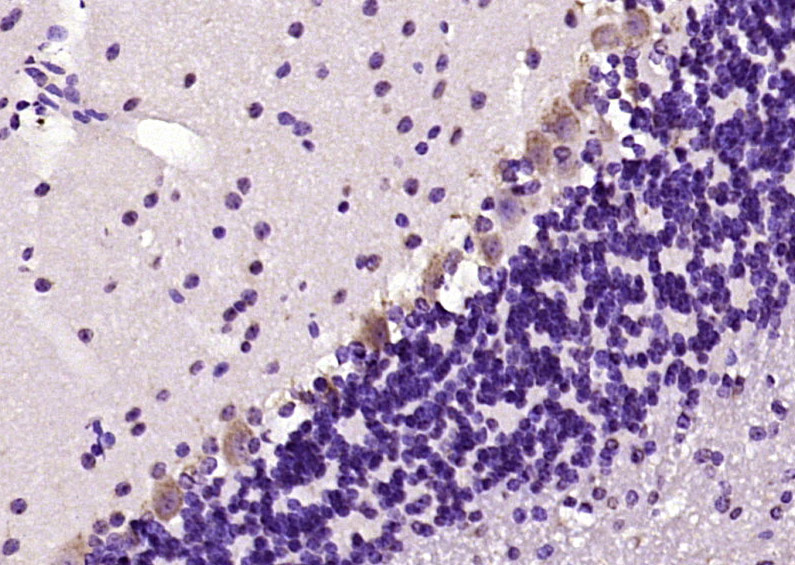

Paraformaldehyde-fixed, paraffin embedded (mouse cerebellum); Antigen retrieval by boiling in sodium citrate buffer (pH6.0) for 15min; Block endogenous peroxidase by 3% hydrogen peroxide for 20 minutes; Blocking buffer (normal goat serum) at 37°C for 30min; Antibody incubation with (phospho-MST4 (Thr190)) Polyclonal Antibody, Unconjugated (bs-10682R) at 1:200 overnight at 4°C, followed by operating according to SP Kit(Rabbit) (sp-0023) instructionsand DAB staining.